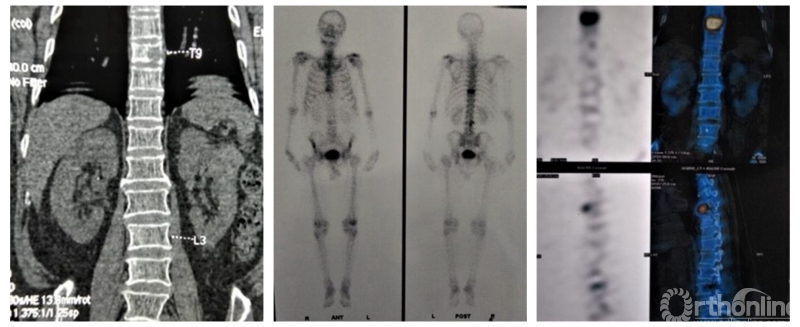

临床上常见引起椎体压缩性骨折的疾病多见骨质疏松、肿瘤(骨髓瘤)、转移癌及炎症(结核)等,其中骨髓瘤极易误诊、漏诊。

骨髓瘤是骨髓中分泌免疫球蛋白的浆细胞的恶性肿瘤。好发于成人有红骨髓的部位:颅骨、髂骨、肋骨、长骨的干骺端和脊柱,占脊柱原发肿瘤的10%,腰椎多见。好发于40~60岁,男女比例2:1。

骨髓瘤的误诊率高达54-100%,常表现为腰痛(需与腰肌劳损、腰椎间盘突出、腰椎结核、骨质疏松症、类风湿性关节炎、骨转移瘤鉴别)、顽固性头痛(与血管神经性头痛区别)、蛋白尿、血尿(区别肾炎、肾肿瘤)、贫血(需与缺铁性贫血、再障、巨幼、白血病鉴别)、肝功能异常(排除慢性肝炎)及其他,如外伤性骨折、肺癌、肺感染等。

由于骨髓瘤临床表现多样,无特异性,且缺乏警惕,同时对复杂多样的临床表现未作全面而细致的分析,及忽略骨髓瘤呈灶性分布和瘤细胞变异大的特点,是引起骨髓瘤误诊、漏诊的主要原因。